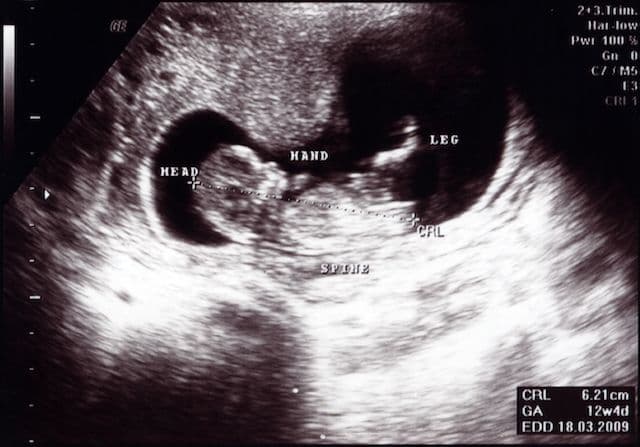

The term crown "crown-rump length" is the measurement of the distance between the top of the embryo and its rump. The CRL can be measured between 7 to 13 weeks and gives an accurate estimation of the gestational age. Dating with the CRL can be within 3-4 days of the last menstrual period.

Femur length increases from about 1.5 cm at 14 weeks to about 7.8 cm at term. (see chart) Similar to the BPD, dating using the femur length should be done as early as possible.

Measures the longest bone in the body and reflects the longitudinal growth of the fetus. Its usefulness is similar to the BPD. It increases from about 1.5 cm at 14 weeks to about 7.8 cm at term. (Chart and further comments) Similar to the BPD, dating using the FL should be done as early as is feasible.